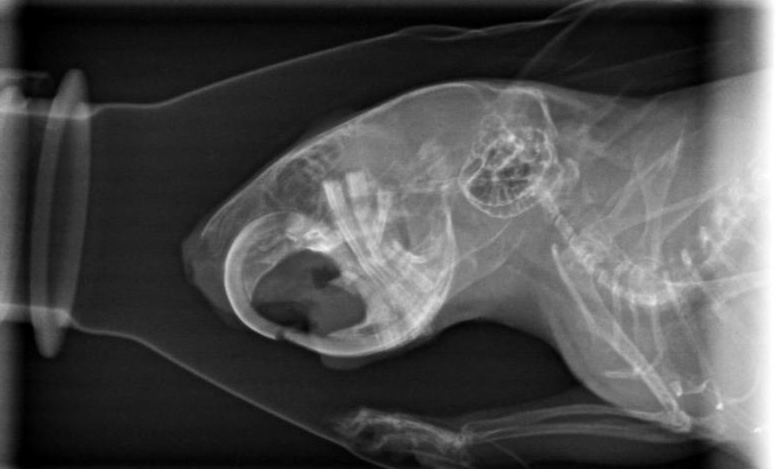

heute gab es doch ein Kontrollröntgen.

Gerade weil es vor Weihnachten super stressig ist, hab ich gesagt sie sollens nur machen, wenns zeitlich rein passt. Und hat es wohl

Hier könnt ihr mit gucken:

Der Unterschied zwischen diesen und den ersten Bildern beträgt übrigens 2 Monate (und ein Tag)

Wow, ohne davon wirklich Ahnung zu haben, sieht man auf den beiden Fotos von oben geröntgt sehr deutlich die positive Entwicklung